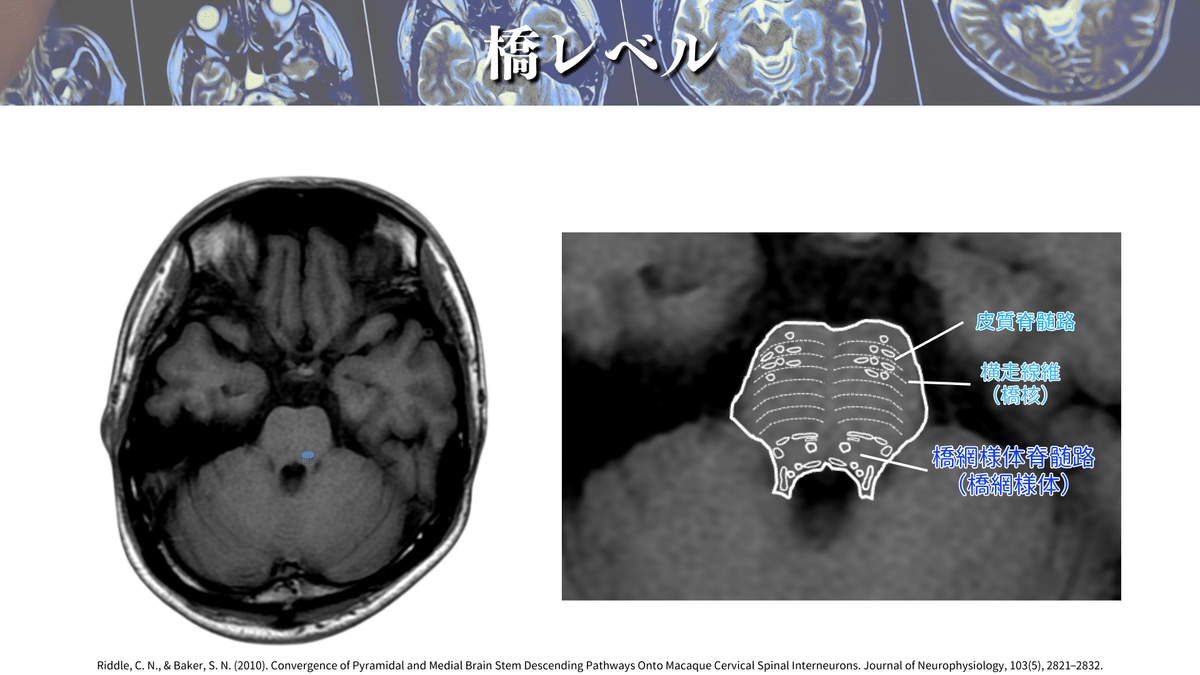

• 皮質網様体路の走行とMRI読影|サギョウ先生